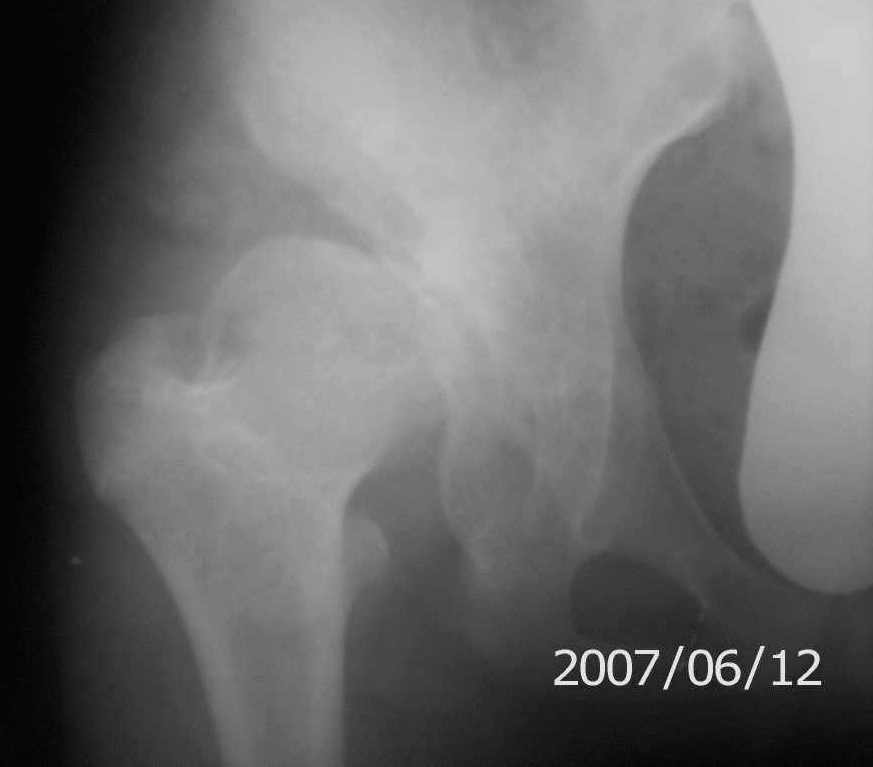

Имя     : п_двивих пряма.jpg